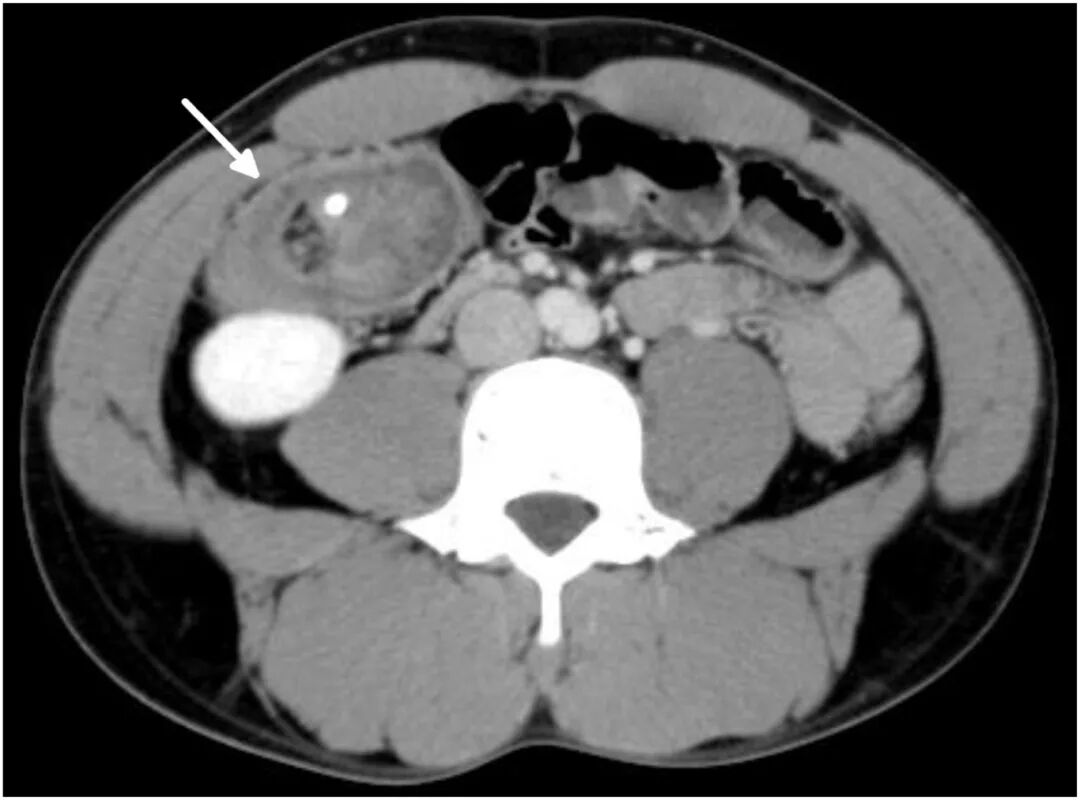

体格检查发现右下腹有明显压痛。患者生命体征在正常范围内,但实验室检查显示白细胞增多(白细胞计数 10100/μL,中性粒细胞占85%)。计算机断层扫描(CT)显示盲肠内陷升结肠引起的阑尾肠套叠(图1、2)。该套叠的头部为一个增大的阑尾,其中包含一枚阑尾粪石。

图2 腹部及盆腔CT检查(冠状位)显示盲肠(箭标所示)套入升结肠(箭头所示)。